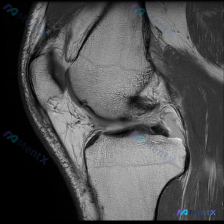

刚整理了一份有意思的膝关节MRI读片病例,临床提示观察到软骨异常,但单张T1加权矢状位影像却没看到明确异常,把分析思路整理出来和大家讨论。 一、病例基本影像信息 这是一张膝关节T1加权矢状位旁矢状位MRI图像,显示区域包括股骨远端、胫骨近端、髌骨、髌腱、Hoffa's脂肪垫和部分后交叉韧带,主要观察...